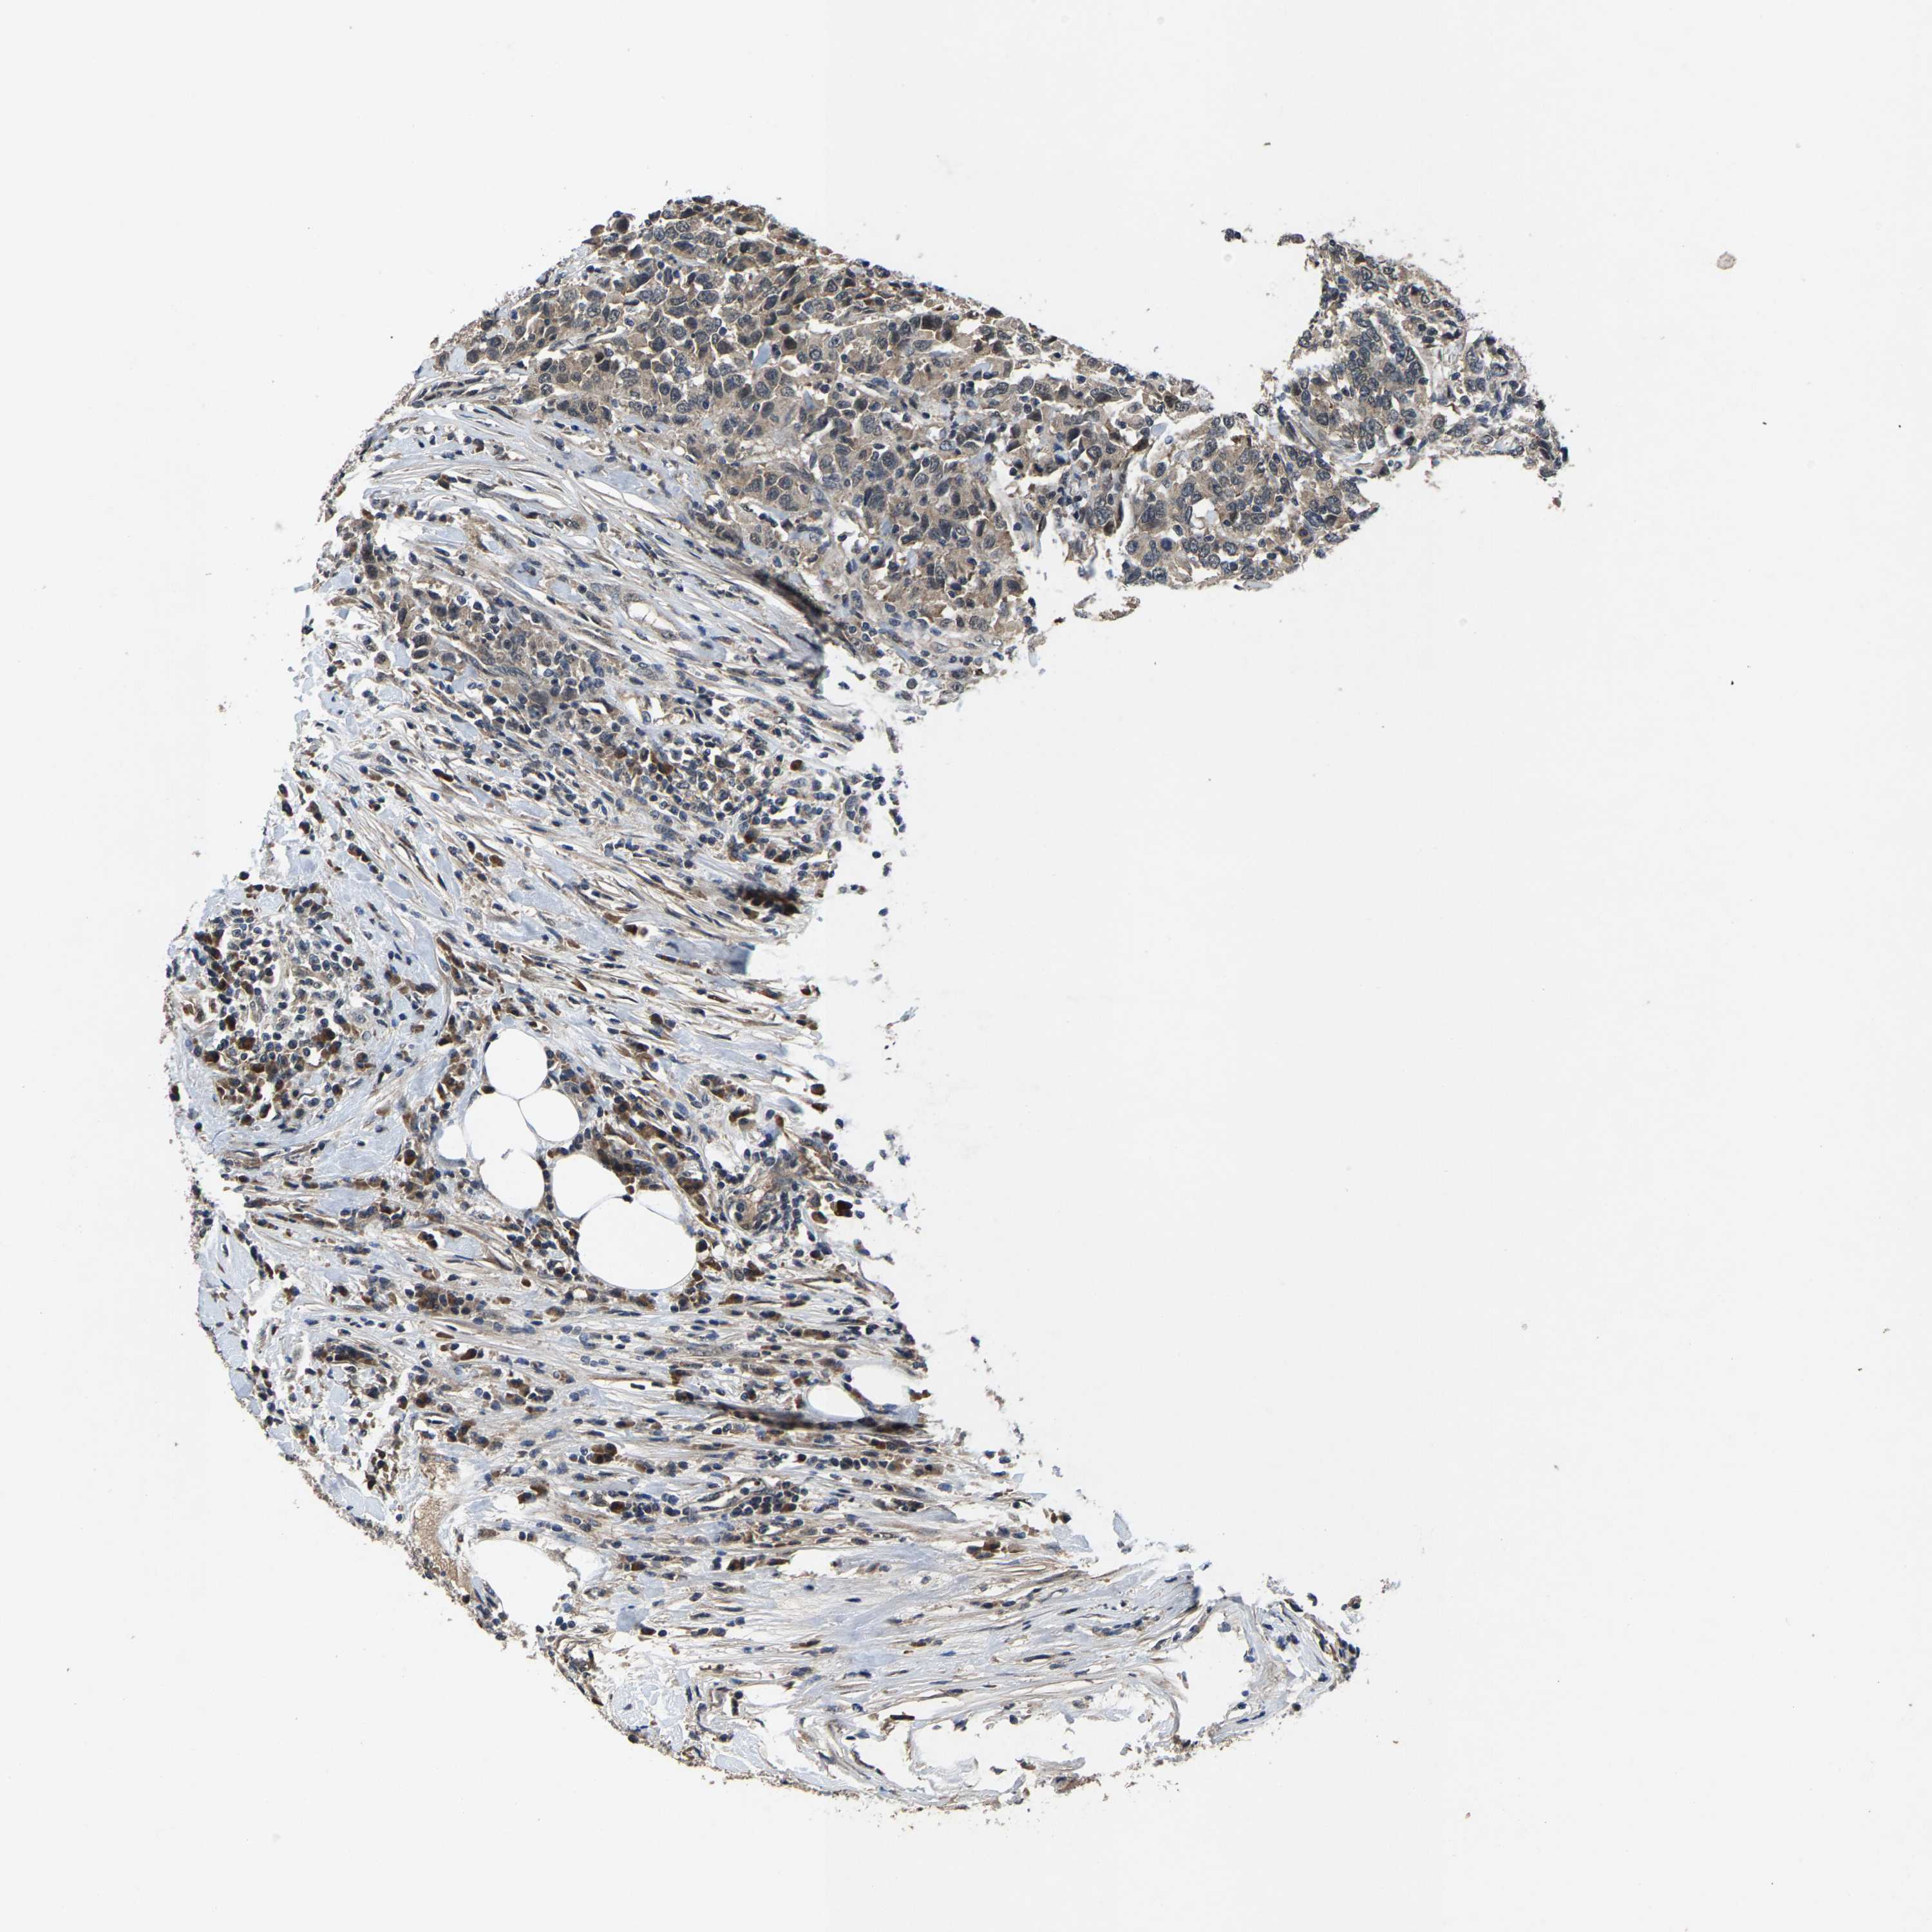

UROTHELIAL CANCER - Protein expressioni

A mouse-over function shows sample information and annotation data. Click on an image to view it in a full screen mode. Samples can be filtered based on level of antibody staining by selecting one or several of the following categories: high, medium, low and not detected. The assay and annotation is described here.

Note that samples used for immunohistochemistry by the Human Protein Atlas do not correspond to samples in the TCGA dataset.

Antibody stainingi

Antibody staining in the annotated cell types in the current human tissue is reported as not detected, low, medium, or high, based on conventional immunohistochemistry profiling in selected tissues. This score is based on the combination of the staining intensity and fraction of stained cells.

Each image is clickable and will lead to virtual microscopy that enables deeper exploration of all samples and also displays staining intensity scores, fraction scores and subcellular localization as well as patient and tissue information for each sample.

Antibody HPA002548

Antibody CAB022718

Staining

High

Medium

Low

Not detected

Intensity

Strong

Moderate

Weak

Negative

Quantity

>75%

75%-25%

<25%

None

Location

Nuclear

Cytoplasmic/membranous

Cytoplasmic/membranous,nuclear

Urothelial carcinoma, High grade

Urothelial carcinoma, Low grade

Adenocarcinoma, NOS